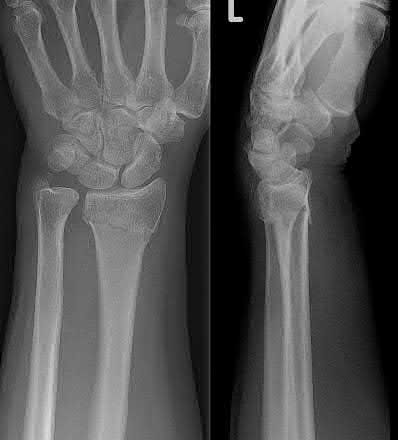

A rare complication of non-displaced or minimally displaced fractures of the distal radius treated with a cast is a delayed rupture of the extensor pollicis longus (EPL) tendon. The EPL is the primary extensor of the interphalangeal joint of the thumb and also assists with metacarpophalangeal extension.

Extensor indicis proprius transfer to the EPL is the most widely used and reported treatment for this condition.

Magnussen et al. reviewed results of EIP transfer following ruptures of the EPL, with 19/21 good results. None of the cases had any loss of independent index finger extension although index extensor strength reduced to half of that of the contralateral side.

Hove et al. reported a similar satisfaction rate following treatment of 15 patients. In his series of 4,400 distal radius fractures treated over a 5 year period, the incidence of delayed tendon rupture following distal radius fracture was 0.3 percent.

A 51-year-old female presents with an acute inability to extend her thumb, four months after she was treated with cast immobilization for a minimally-displaced distal radius fracture. What is the most appropriate treatment at this time?